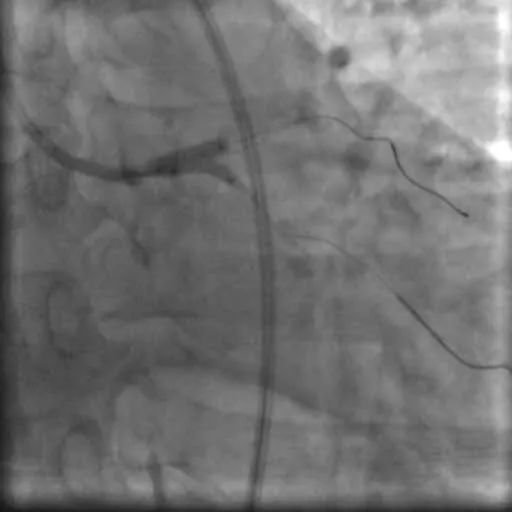

入院后,杨大爷很快在心血管介入中心进行了冠状动脉造影及血管内超声检查术,结果显示:左主干末端至前降支近段,回旋支开口都有严重狭窄且伴钙化。如果再推迟入院几天,很有可能发生猝死。

赵晓辉副主任立即决定采用“支架内球囊锚定技术”,很快球囊便送过回旋支开口,然后与前降支支架内的后扩球囊对吻成功。

造影及血管内超声显示两枚支架均贴壁良好,前降支及回旋支开口管腔狭窄显著改善,前向血流良好。

造影图